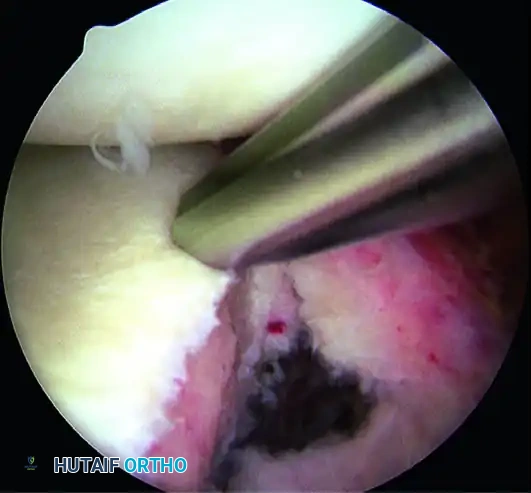

5. Recreating the Anterior Bumper

Proceed superiorly, placing the second and third double-loaded anchors. Firmly secure the sutures, compressing the capsuloligamentous complex to the abraded bone surface. This "loop and knot fixation" rolls the tissue up onto the glenoid face, recreating a robust anterior soft-tissue bumper.

D, Knots tied re-creating soft tissue bumper.

B, Restored anterior labral bumper (arthroscopic view).

C, Restored anterior labral bumper (alternate angle).

6. Rotator Interval Closure

If the patient exhibits baseline hyperlaxity and a significant sulcus sign that persists after the Bankart repair, a rotator interval closure is mandatory to address the superior glenohumeral ligament (SGHL) and coracohumeral ligament (CHL) laxity.

- Withdraw the anterior central cannula just outside the capsule.

- Pass a crescent Spectrum needle through the IGHL, several millimeters into the ligament, and into the joint.

- Maintain one limb outside the capsule. Retrieve the intra-articular limb using a penetrator device at the level of the SGHL.

- Tie the sutures extracapsularly using an SMC knot. Generally, two sutures are sufficient. The slight loss of external rotation is a necessary trade-off for the added inferior stability.

Completed Bankart repair with three anchors and capsule plicated inferiorly. Rotator interval is closed.

Final Construct Verification

Evaluate the final repair. The drive-through sign should be eliminated, the humeral head should be centered on the glenoid, and a prominent anterior bumper should be visible.